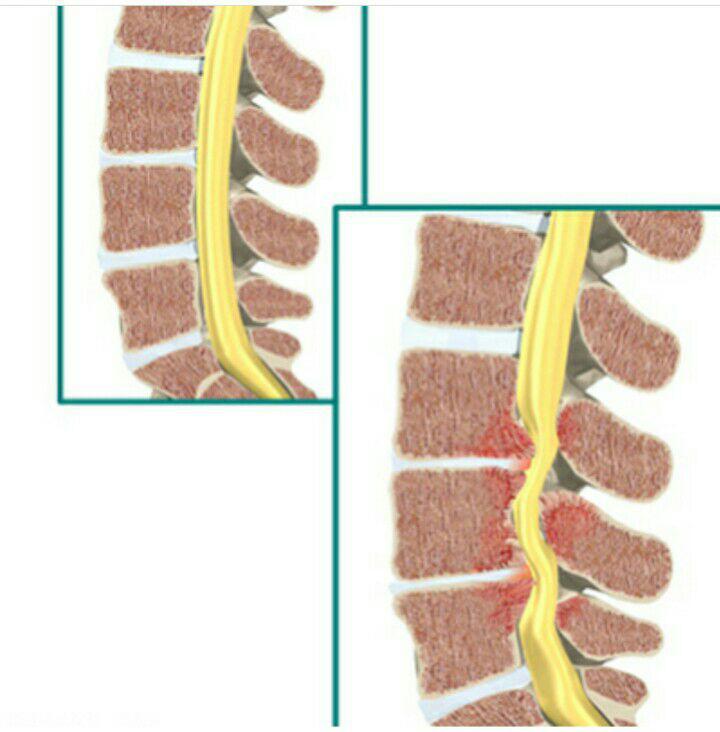

-لیزر(جراحی بسته) دیسک کمری

-درمان تنگی کانال نخاعی غیرقابل جراحی

استفاده از روشهایی مانند تزریقات تخصصی (مانند اپیدورال، بلوک عصبی)، طب سوزنی، فیزیوتراپی، تحریک الکتریکی عصب و روشهای کم تهاجمی جراحی.